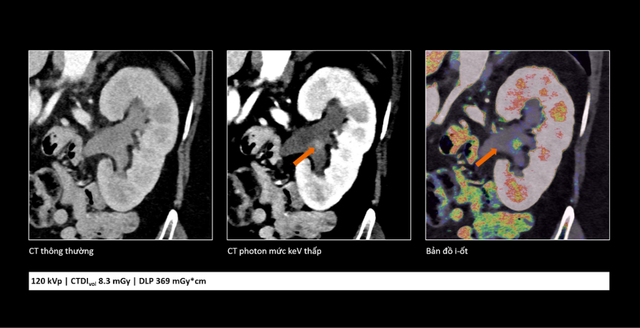

So sánh cho thấy công nghệ cắt lớp vi tính lượng tử không chỉ giúp hình ảnh rõ hơn mà còn cung cấp thêm thông tin, hỗ trợ bác sĩ đánh giá tổn thương chính xác hơn.

Bên cạnh khả năng cải thiện chất lượng hình ảnh, công nghệ cắt lớp vi tính lượng tử còn giúp giảm đáng kể liều tia X và lượng thuốc cản quang sử dụng. Điều này góp phần tăng mức độ an toàn cho người bệnh, đặc biệt với những người có nguy cơ suy thận hoặc mắc bệnh lý nền phức tạp.